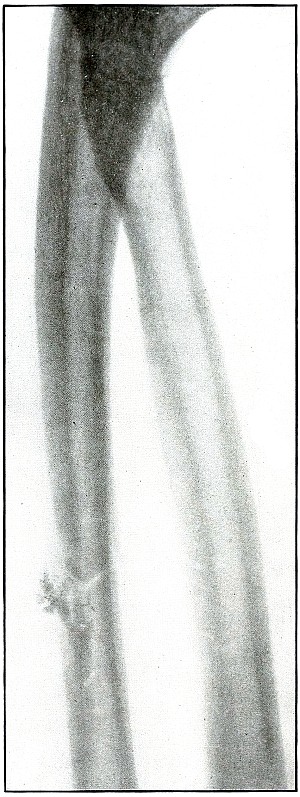

| 21. |

Gunshot fracture, radius and ulna |

52 |

| 22. |

Gunshot fracture, radius and ulna |

54 |

| 23. |

Gunshot fracture, radius and ulna |

56 |

| 24. |

Gunshot fracture, radius and ulna |

58 |

| 25. |

Gunshot fracture, radius |

60 |

| 26. |

Gunshot fracture, radius |

62 |

| 27. |

Gunshot fracture, radius |

64 |

| 28. |